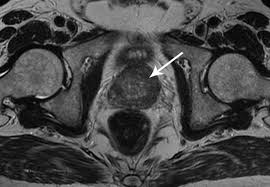

Prostate Cancer Imaging:

Some Adult men may need added tests to find out Should the cancer has distribute beyond the prostate. These can incorporate ultrasound, a CT scan, or an MRI scan (seen listed here). A radionuclide bone scan traces an injection of small-level radioactive substance to help detect cancer which includes spread on the bone.During the MRI scan proven below, the tumor is the eco-friendly, kidney-formed mass in the center, next to the prostate gland (in pink).